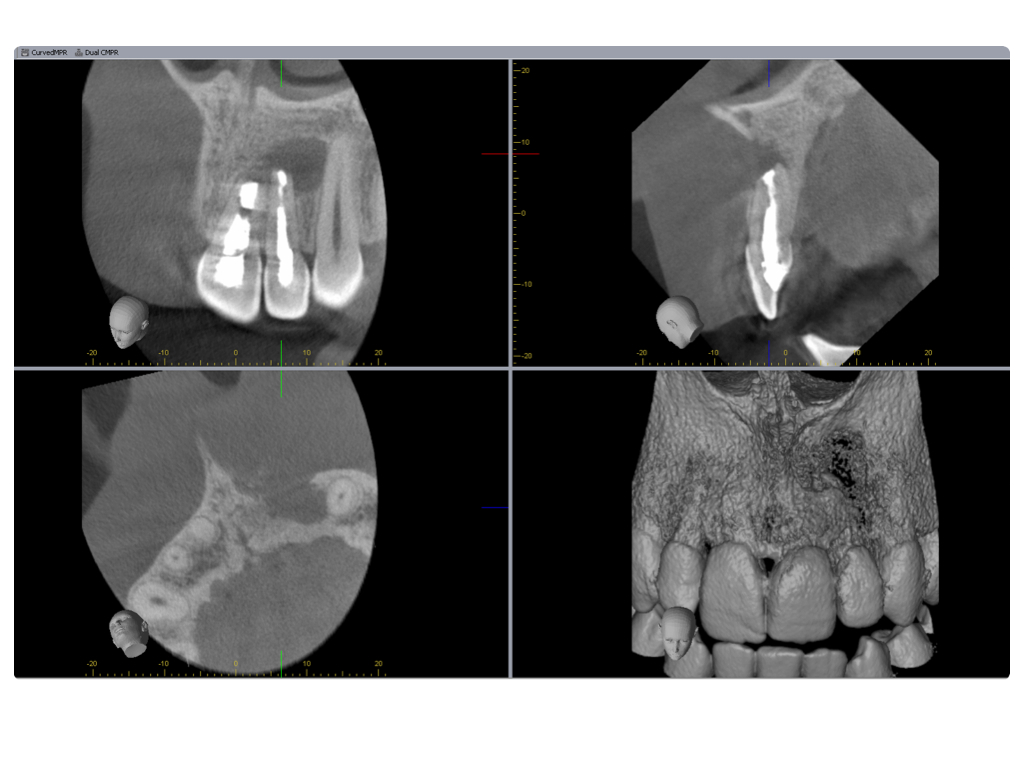

Einbahnstraße WSR (2)

DVT